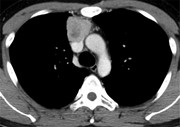

Superior vena cava repair with left brachiocephalic vein flap

Hiroyoshi Tsubochi and others

Journal of Surgical Case Reports, Volume 2016, Issue 3, March 2016, rjw015, https://doi.org/10.1093/jscr/rjw015